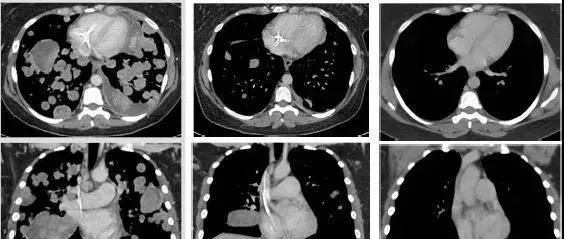

未分化肉瘤 41岁女性 治疗前:患者的肿瘤细胞已广泛转移到肺部,并将很快充满肺部。治疗后,呼吸困难和低氧血症可以迅速得到解决。2个周期后,大多数肿瘤消失,12个周期后,肿瘤组织几乎完全消失!